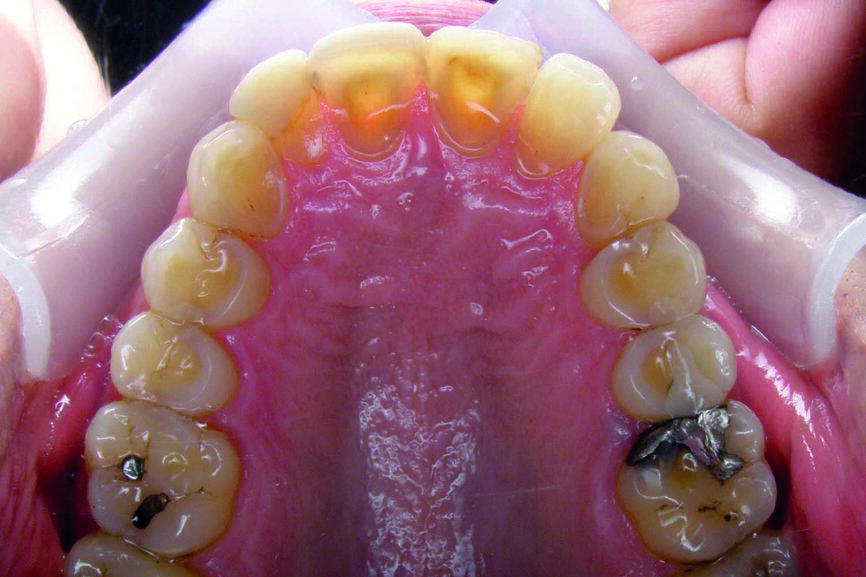

Examen des arcades

D’un point de vue dentaire le patient présente une Classe II division 1, avec une classe II molaire complète et une classe II canine.

- Présence d’un overjet et d’une supraclusion résiduelle.

- L’arcade supérieure est régulière mais les incisives sont en vestibulo version importante.

- L’arcade inférieure présente un encombrement dans le secteur antérieur associé à une version vestibulaire.

- Les milieux correspondent.